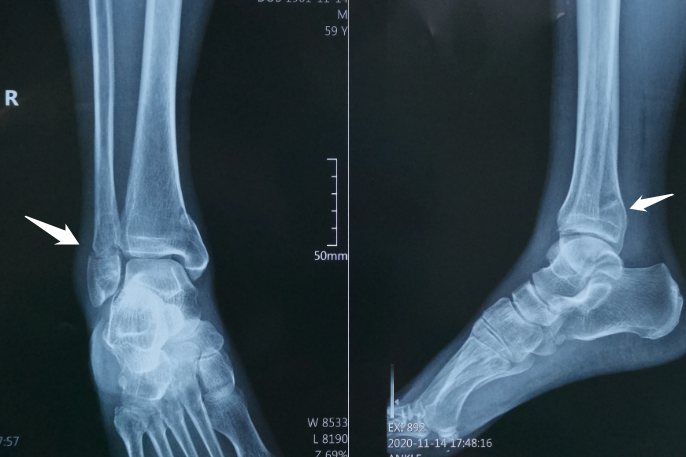

踝部骨折:

踝部骨折会导致踝关节出现活动明显受限,伴有明显的肿胀、皮下瘀斑和疼痛感觉。由于不同的暴力方向,可以形成明显的内收或是外旋畸形。